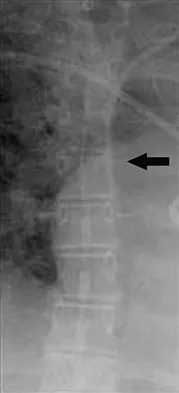

A 65-year-old woman has nausea, vomiting, and abdominal distention after undergoing total knee arthroplasty 48 hours ago. An abdominal radiograph is shown in Figure 14. Associated risk factors for this disorder include

Explanation

The prevalence of postoperative ileus associated with total joint arthroplasty has been reported to be as high as 3%. Metabolic abnormalities such as hypokalemia are believed to contribute to the onset of ileus and Ogilvie's syndrome (acute pseudo-obstruction of the colon). Prolonged bed rest also has been associated with the development of ileus and Ogilvie's syndrome. Untreated Ogilvie's syndrome can result in cecal perforation. Ileus usually is not accompanied by mechanical obstruction. Antibiotic administration and the type of anesthesia used have not been correlated with development of ileus. Administration of warfarin has been associated with elevated prothrombin time/partial thromboplastin time and international normalized ratio levels when ileus is managed with a nasogastric tube and suction. Metabolic imbalances must be corrected to reverse the ileus process. Iorio R, Healy WL, Appleby D: The association of excessive warfarin anticoagulation and postoperative ileus after total joint replacement surgery. J Arthroplasty 2000;15:220-223.